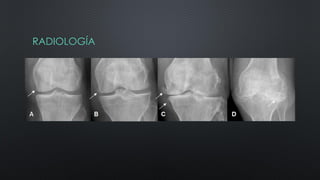

RADIOLOGÍA

¿COMO SOLICITAR LAS

PLACAS?

• RX DE PELVIS AP Y DE CADERAS EN ABDUCCIÓN

• RX DE RODILLA DE PIE AP-L Y AXIAL DE ROTULA

( EN CARGA)

• OTROS ESTUDIOS COMPLEMENTARIOS:

ARTROCENTESIS, ESTUDIO BIOQUÍMICO

SIGNOS

• DISMINUCIÓN DEL ESPACIO ARTICULAR

• ESCLEROSIS SUBCONDRAL

• OSTEOFITOS

• QUISTES SUBCONDRALES

RADIOLOGÍA ¿COMO SOLICITAR LAS PLACAS? •RX DE PELVIS AP Y DE CADERAS EN ABDUCCIÓN • RX DE RODILLA DE PIE AP-L Y AXIAL DE ROTULA ( EN CARGA) • OTROS ESTUDIOS COMPLEMENTARIOS: ARTROCENTESIS, ESTUDIO BIOQUÍMICO SIGNOS • DISMINUCIÓN DEL ESPACIO ARTICULAR • ESCLEROSIS SUBCONDRAL • OSTEOFITOS • QUISTES SUBCONDRALES